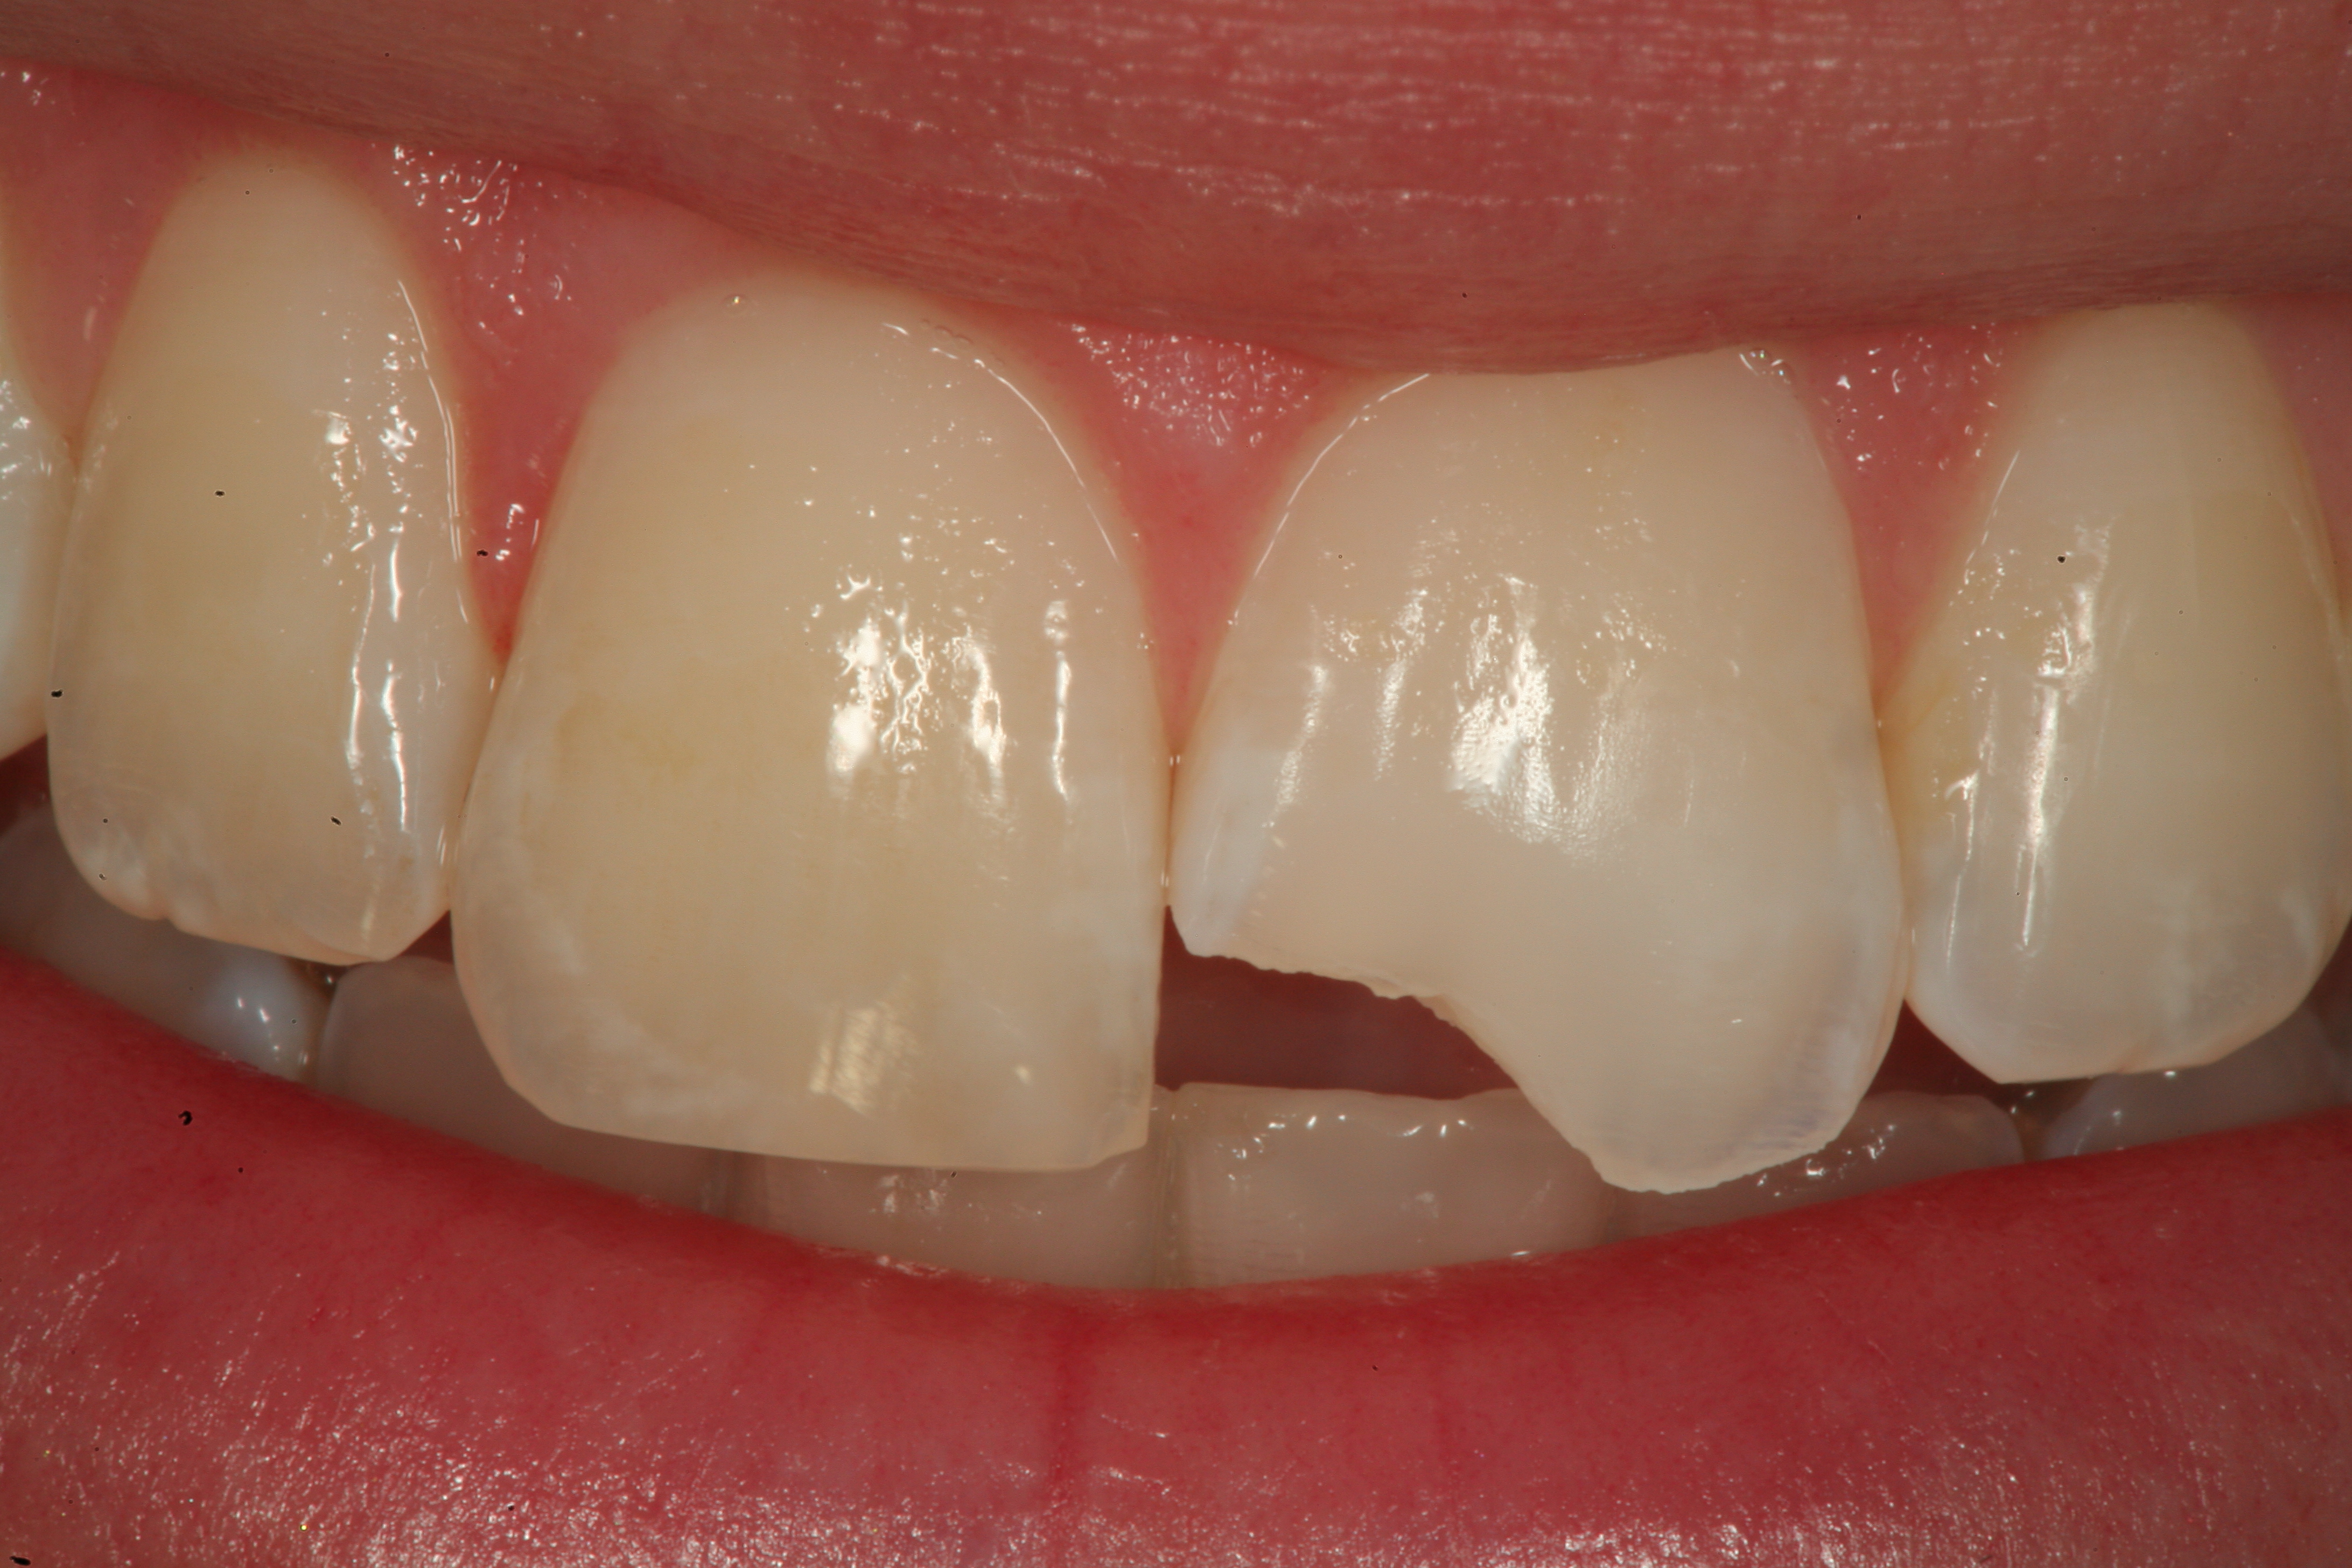

Fig 12. A Class IV mesial incisal fracture is shown from the facial aspect on tooth No. 9.

Figure 12